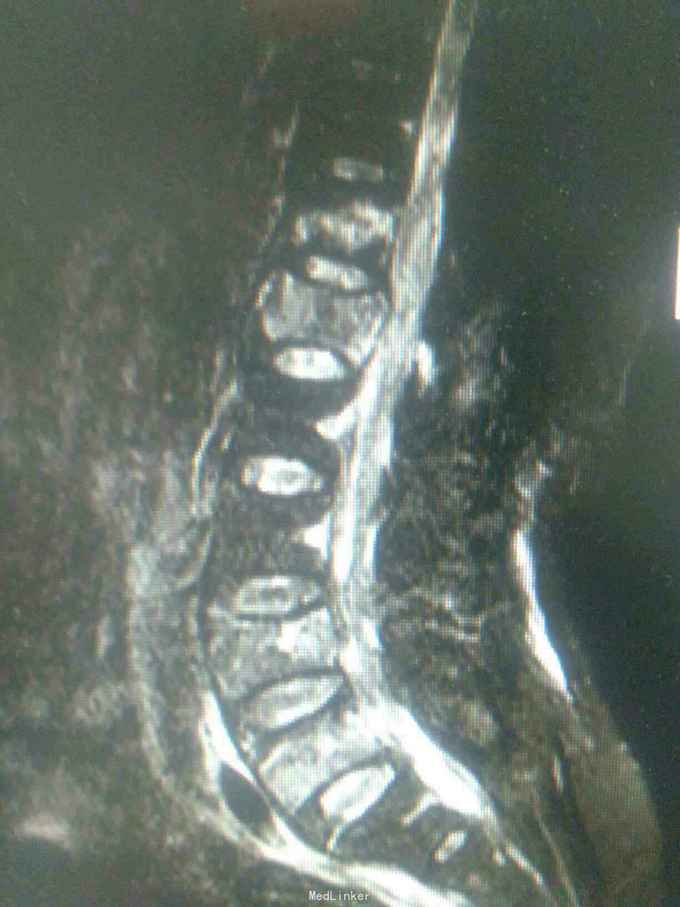

患者因高处坠落致腰痛部疼痛,双下会活动受限9小时入院。患者9小时前从3米高处坠落,腰骶部先着地,即时觉双下肢麻木,不能活动。

查体腰背部压痛,双下肢肌力0级,肌张力减低,会阴区,双下肢痛觉减低,触觉,精细觉正常,腱反射未引出,肛门反射消失,括约肌松弛。

诊断腰1,腰4椎体爆裂性骨折,腰5椎体压缩性骨折,脊髓圆锥损伤双下肢截瘫。患者入院后48小时内行了腰椎后路腰1.4椎体切开复位椎弓根钉内固定,腰1椎板切除,椎管扩大成形,横突间植骨融合术。